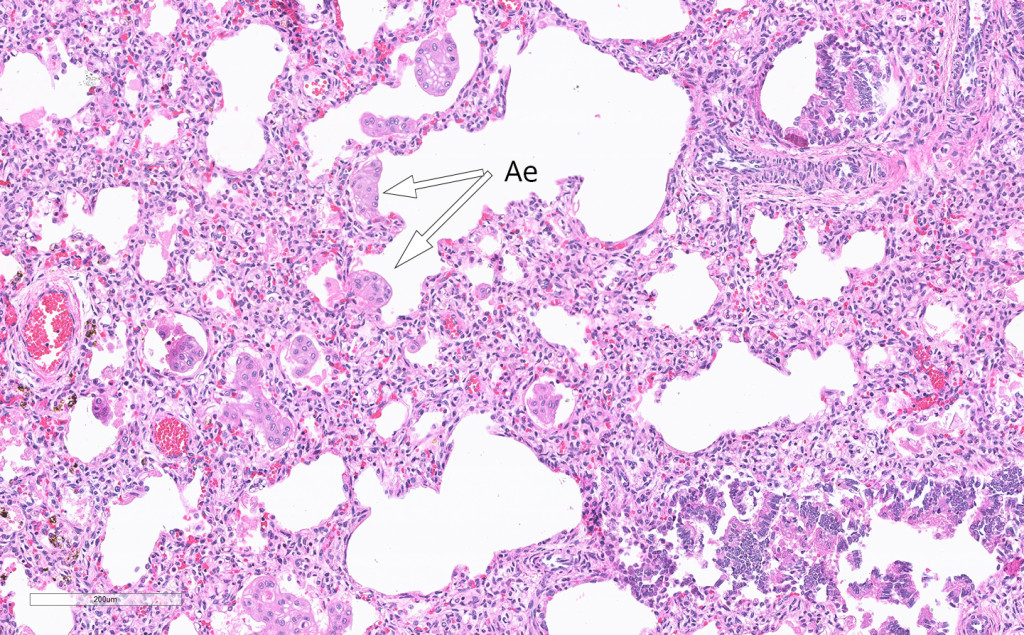

Microscopy of the lungs revealed flakes of amniotic epithelium that had been aspirated in utero (Fig. 3). The stomach was dilated and contained a large volume of material. There was thickening of the pylorus and it was not possible to insert a probe into the duodenum. A spleen sample showed absence of trisomy 13, 18 and 21.

Figure 3 Haematoxylin and eosin-stained lung section with amniotic epithelium (Ae) in the intra-alveolar space

Examination of the placenta provided no evidence of abruption. The absence of nucleated erythrocytes suggests that the child's severe anaemia resulted from an acute catastrophic event, a fetal haemorrhage from a damaged umbilical cord artery. Our interpretation of events is that the small intestinal atresia resulted in reflux of stomach contents into the amniotic fluid, which led to necrosis of the cord and Wharton's jelly, and almost complete destruction of the muscular part of the arteries. This resulted in catastrophic fetal haemorrhage. The presence of aspirated amniotic epithelium in the child's lungs supports this interpretation (Fig. 3). The cord's amniotic epithelium had been torn off and then aspirated, explaining its presence in the pulmonary alveolar space.